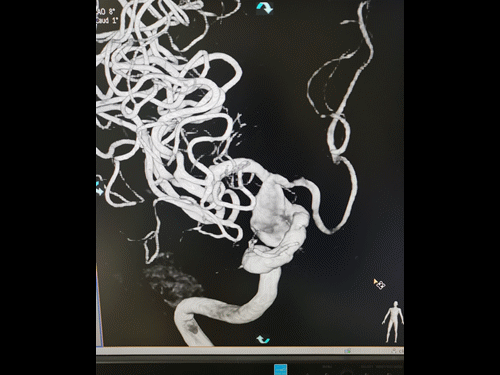

由于颈部血管迂曲明显,选择Neuron MAX 6F 088长鞘顺利到达右颈内动脉C1末端做近端支撑。Synchro 0.014 200微导丝及XT-27微导管引导CAT 5(Catalyst 5)导管同轴越过右颈内动脉末端动脉瘤至右大脑中动脉瘤M1末端后撤出微导丝微导管,保留CAT 5导管。

选取Surpass Streamline 5mm╳40mm经CAT 5导管释放。由于血管迂曲,支架与CAT 5导管摩擦较大,Surpass Streamline无法推出。

图5

将Neuron MAX 6F 088长鞘尽可能送达右颈内动脉岩骨段,将Surpass Streamline在体外推送至支架导管头端MARK点,再经CAT 5导管释放。考虑动脉瘤颈宽大,载瘤动脉瘤样改变,Surpass Streamline远端定位右侧大脑中动脉M1中远段,结合推拉技术,顺利释放Surpass Streamline,并行导丝充分按摩。

图6